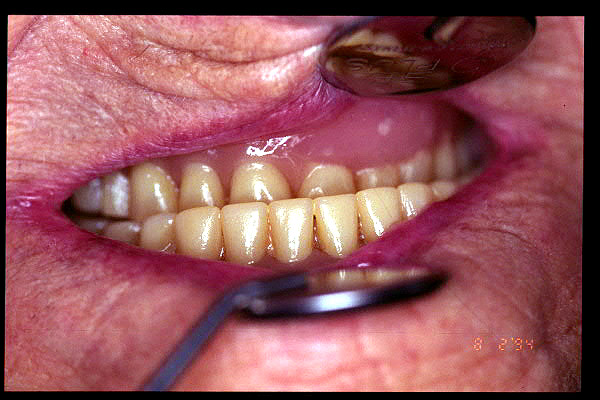

CM Prótesis dental con mala oclusión y con desgaste excesivo

CM El paciente tiene que protuir la mandíbula para poder ocluir